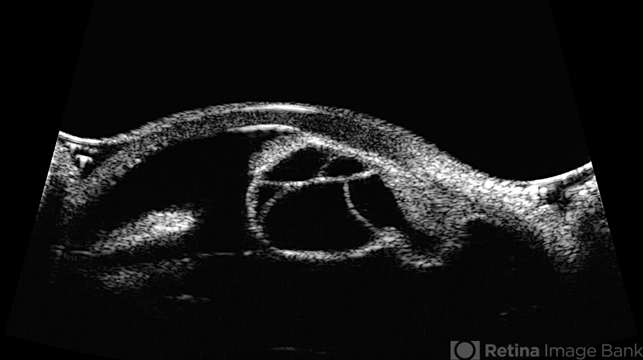

- cyst, idiopathic cysts, ultrasound biomicroscopy, cystic lesion

Ultrasonography device

Ellex Eye Cubed - Description

- 74 year old female with idiopathic iris cyst encroaching visual axis. Lesion is cystic with baseline internal reflectivity, unequivocal growth since first exam in 2022. Pt remains asymptomatic, will continue to observe.